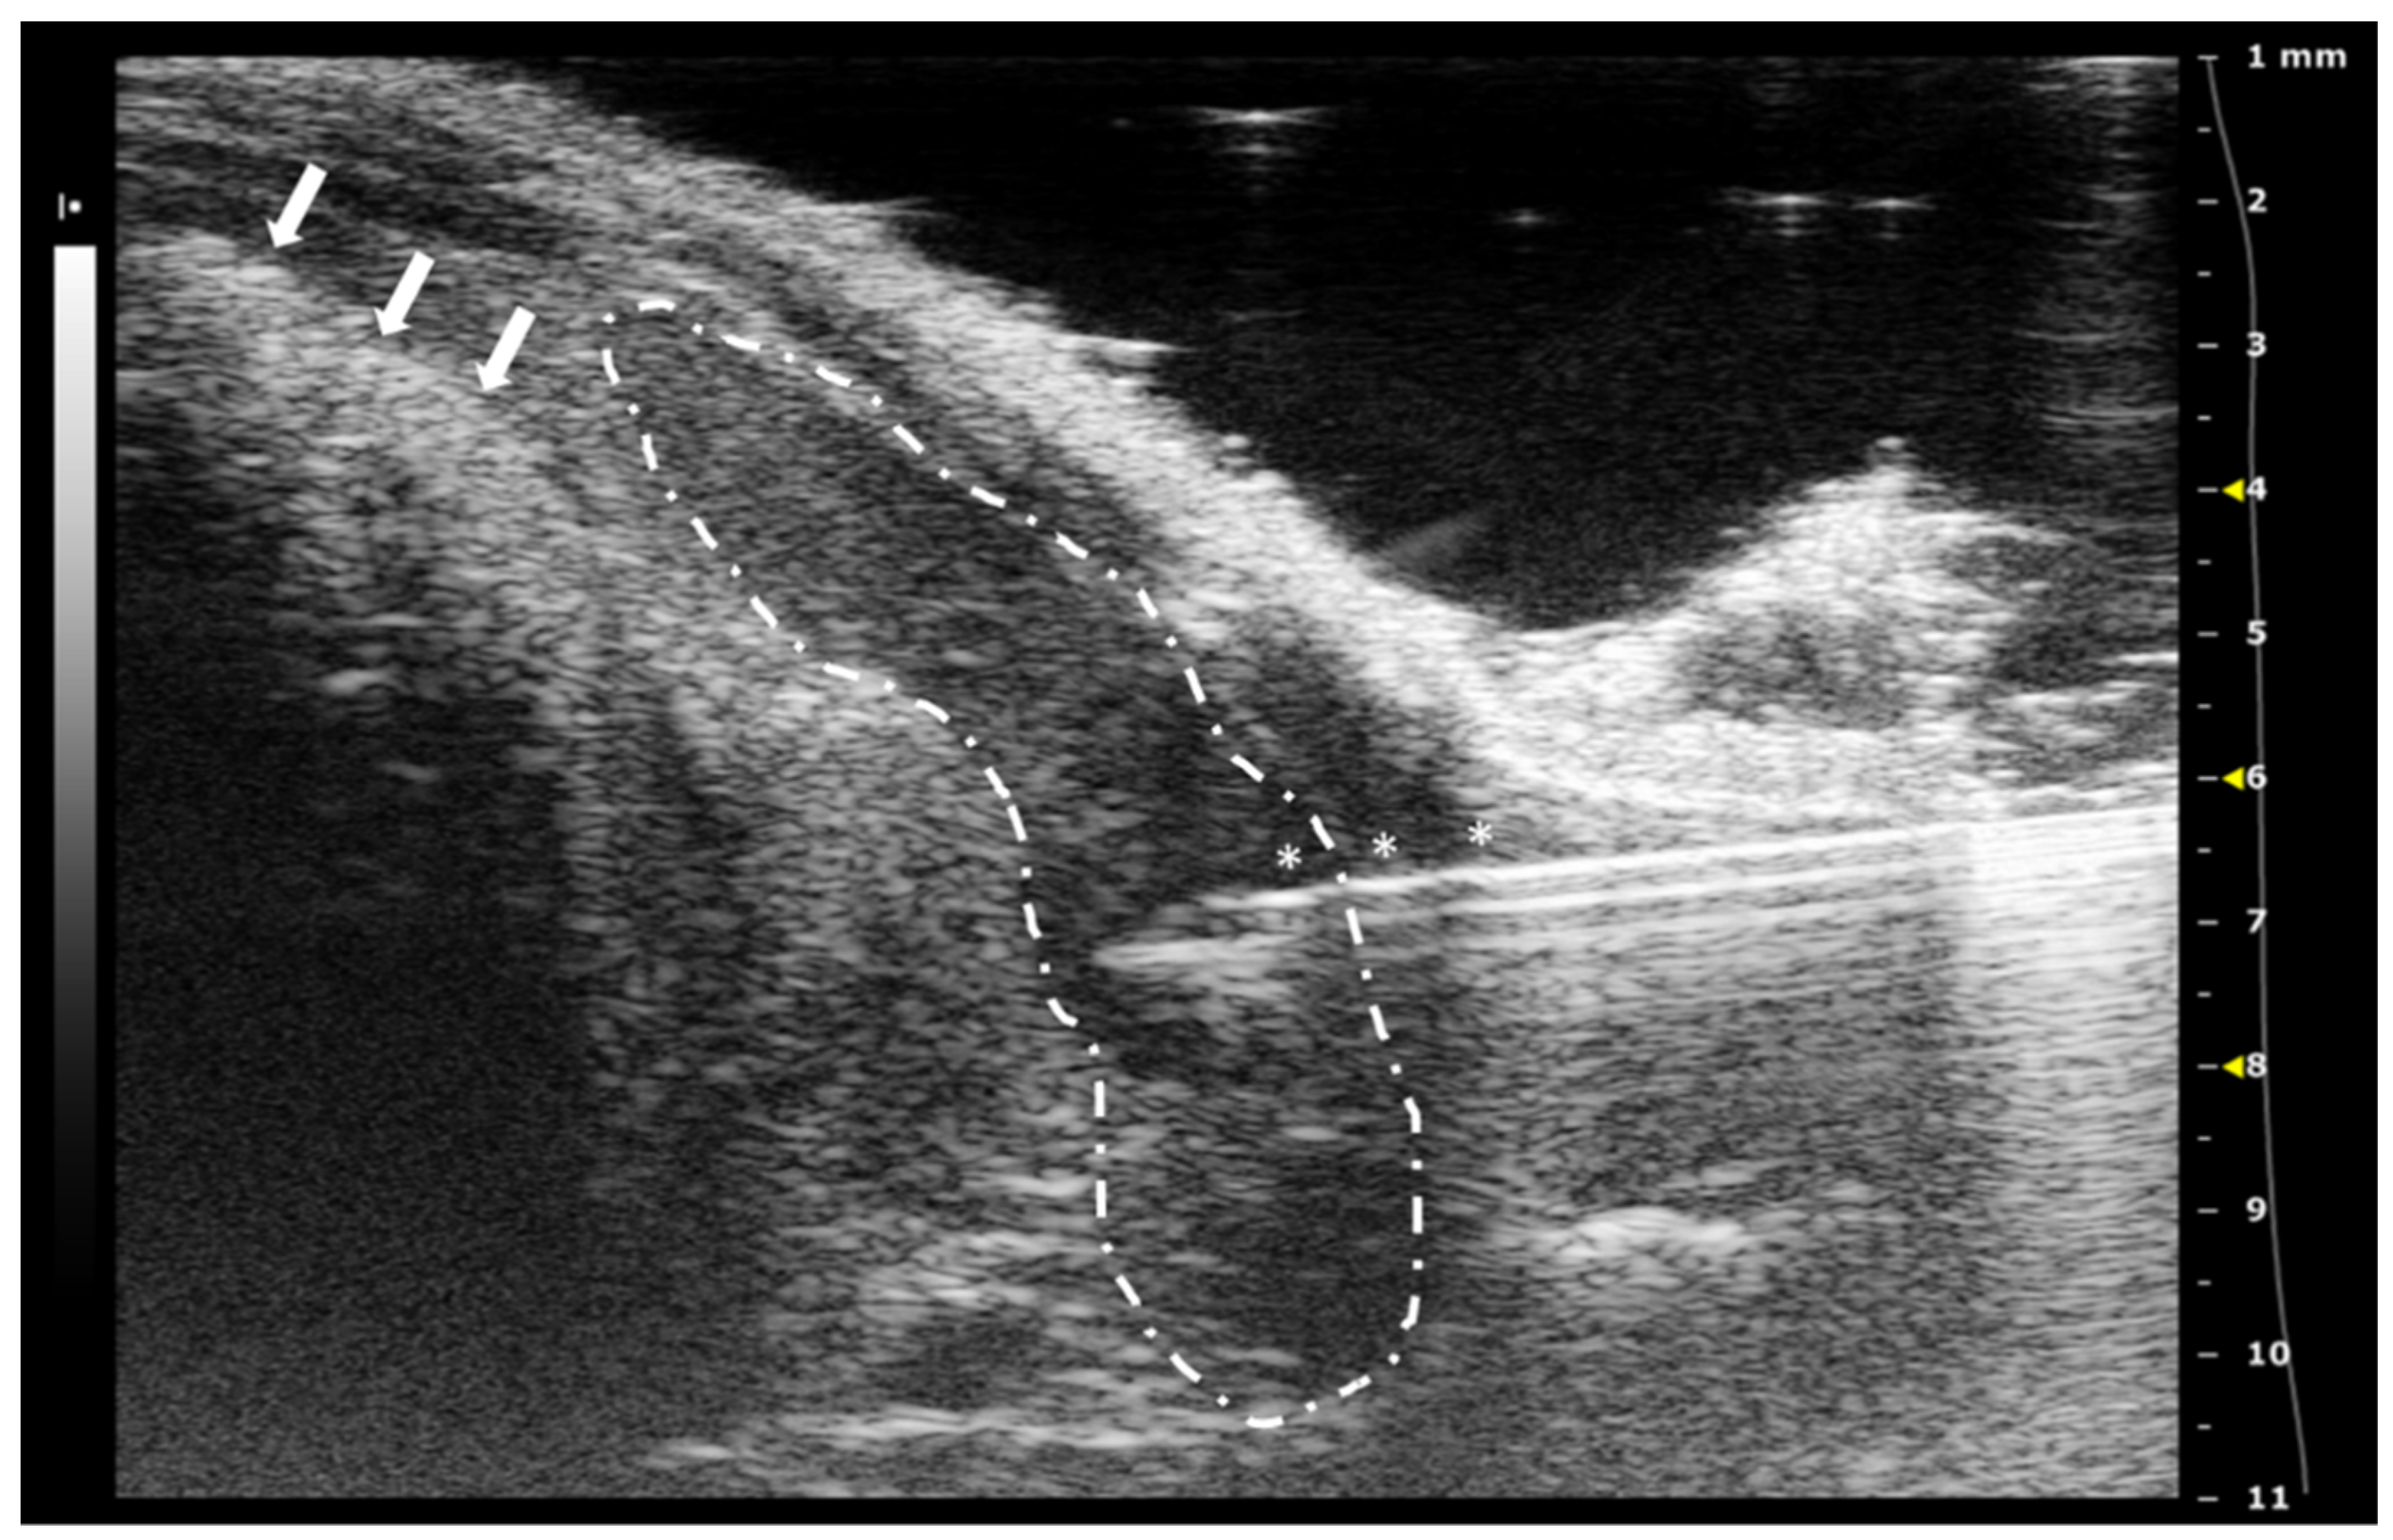

For intrathyroidal injections, a ventral approach is required, positioning the mouse in ventral recumbence and removing the hair of the neck and cranial part of the thorax. The front limbs are fixed with tape in a caudal position, close to the ribs. Intubation of the animal is not required and anesthesia can be supported with a facial mask. After the application of ultrasonographic gel, the scan starts locating the trachea in transversal view at the hyoid bone level. It is recognized due to the acoustic shadow produced by the intratracheal air. Moving the probe caudal, the salivary glands will appear as two superficial, bilateral, hypoechoic, and big structures. At this level, we will need to slightly increase the pressure of the probe against the neck for improving the visualization of deeper structures. Going caudal, a muscular band will appear in the middle line, ventral to the trachea, followed by two bilateral structures, the sternohyoideus and sternothyroideus muscles. The carotid arteries and jugular veins will be visible at this point. The first ones are smaller but have a pulse. We can check the blood flow direction using the Color Doppler mode of the ultrasound system. In a standardized position of the probe (left side of the probe placed over the right side of the animal), the arterial flow should be colored in red and the jugular veins should appear in blue (Figure 2).

The thyroid glands will be located at this level, dorsal and slightly medial to the neck vessels. In a standardized exam, they will appear under the vessels. They are composed of soft tissue, so the echogenicity will be lower than the salivary glands but higher than the vessels. Their shape is irregularly ellipsoidal. The best approach for the puncture is lateral, placing the needle under the ultrasound probe. If the needle is placed correctly in the injection support, we will see it coming from the lateral of the screen (Figure 2). The hardest part of the injection is piercing the skin and for this purpose, we can use forceps for immobilizing the skin. The maximum volume we can inject is low due to the organ size, so more than 10 to 20 microliters in each gland is not recommended [18,19,20].

Figure 2. Thyroid gland injection. (A) Doppler mode of the medium level of the neck, where the jugular veins are colored in blue while the carotid arteries in red. Salivary glands marked with a black asterisks and neck muscles with a white arrow. (B) B mode during the thyroid injection. The needle is marked with white asterisks, and the thyroid gland is surrounded by a dashed line. Trachea cartilage is signaled with white arrows. Images acquired with 40 MHz frequency in B mode and 32 MHz in Doppler mode.